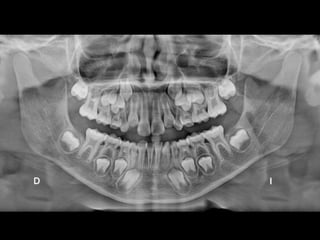

RADIOGRAFÍAS PANORÁMICAS